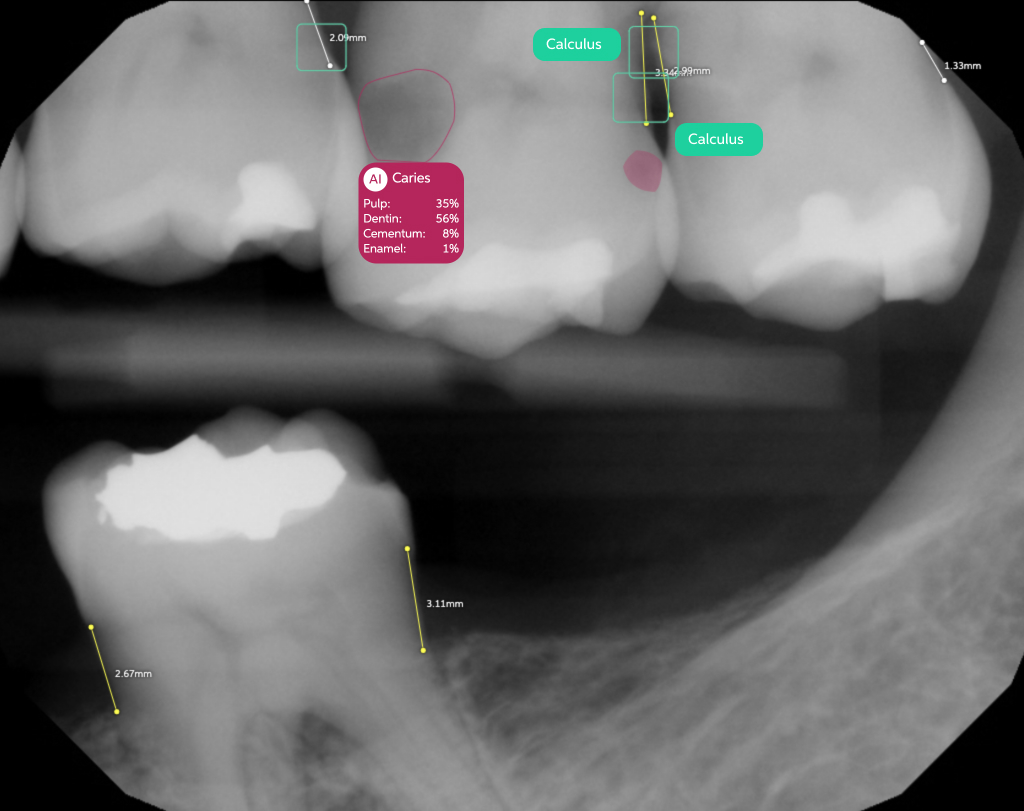

Pearl’s AI is trained on world's largest collection dental x-rays to detect a greater range of pathologies, existing restorations and natural anatomy than any solution of its kind, enabling 37% more accurate x-ray evaluations.

Color-coded detections, educational tooth part maps and quantitative results give patients an objective, clear and data-based foundation for trust in your findings––trust that boosts case acceptance by 24% on average.